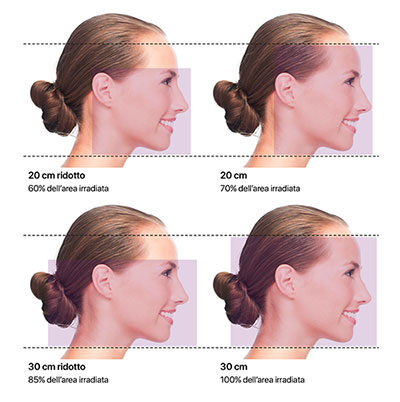

Collimation intelligente

Le collimateur primaire servo-commandé (breveté) permet de sélectionner la région exacte à exposer aux rayons X.

Le collimateur secondaire pour les projections téléradiographiques est intégré dans le module rotatif et permet un accès facilité avec un encombrement minimum (brevet en instance).